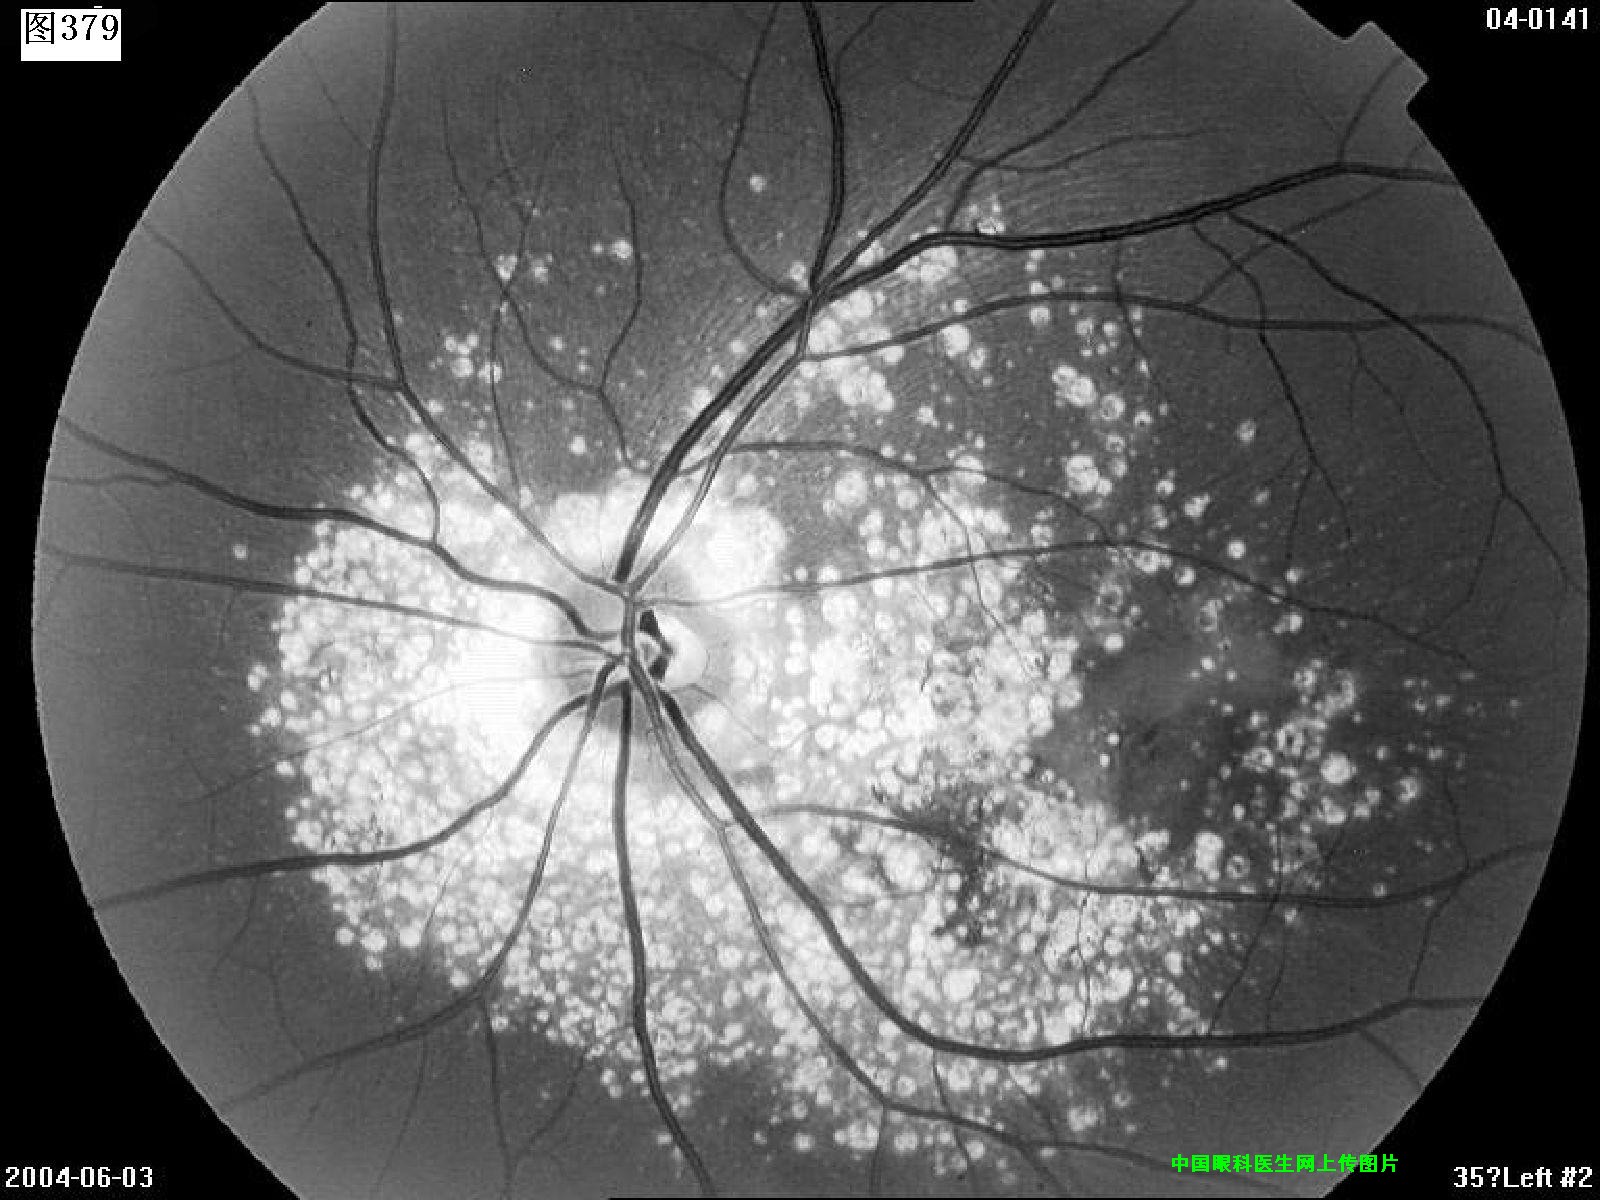

377 378 379 380